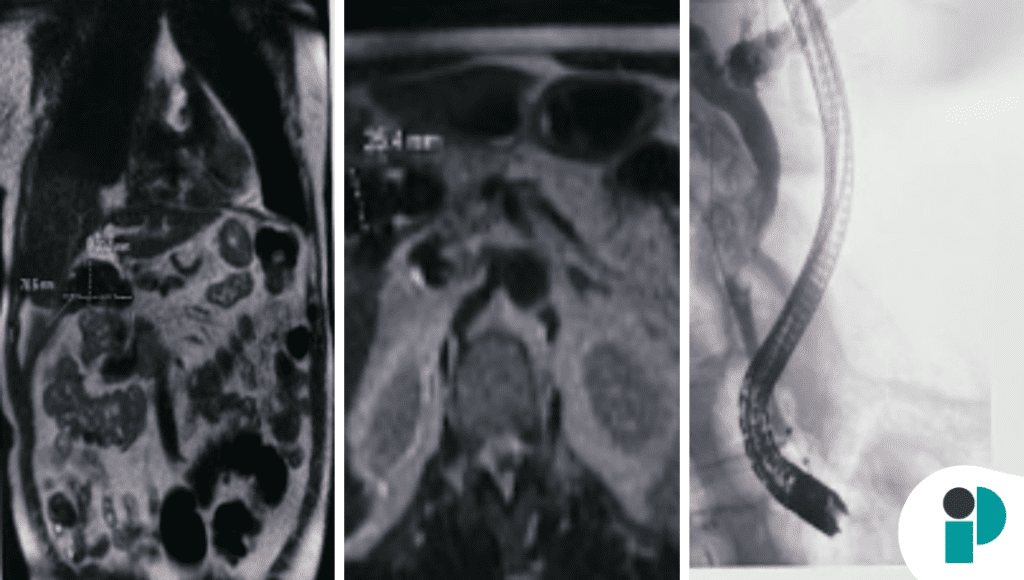

El ultrasonido abdominal evidenció colelitiasis, mientras que la tomografía mostró inflamación perivesicular. Posteriormente, la colangiopancreatografía por resonancia magnética (MRCP) reveló compresión del conducto hepático común sin dilatación biliar marcada, un hallazgo sugestivo de síndrome de Mirizzi en presentación atípica.

El diagnóstico se confirmó mediante colangiopancreatografía retrógrada endoscópica (ERCP), que evidenció un cálculo impactado en el conducto cístico causando compresión extrínseca del conducto hepático común.

Se realizó colocación de stent biliar mediante ERCP, seguida de colecistectomía laparoscópica, con evolución clínica favorable.